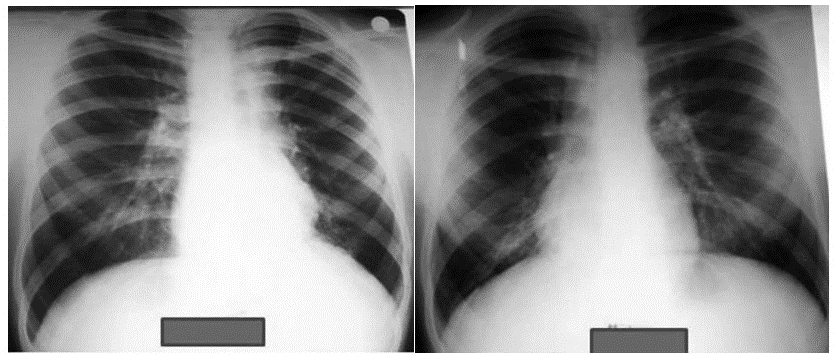

Chest x-ray showing dense opacity pleural effusion in the lower left lung of primary pulmonary TB

Pulmonary tuberculosis affects the lungs and often causes symptoms such as a chronic cough that lasts up to 3 weeks or more, chest pain, blood in cough (hemoptysis), weight loss, low-grade fever, and night sweats. When the infection spreads to other parts of the body, it is known as secondary tuberculosis.